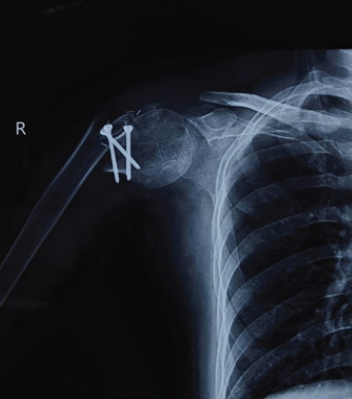

Spontaneous Remodeling of Posterior Sternoclavicular Joint Dislocations in Skeletally Immature Patients: A Case Report

Abdalla O. Abdalla , Eoin Fahey , Rebecca Lyons , David Morrissey